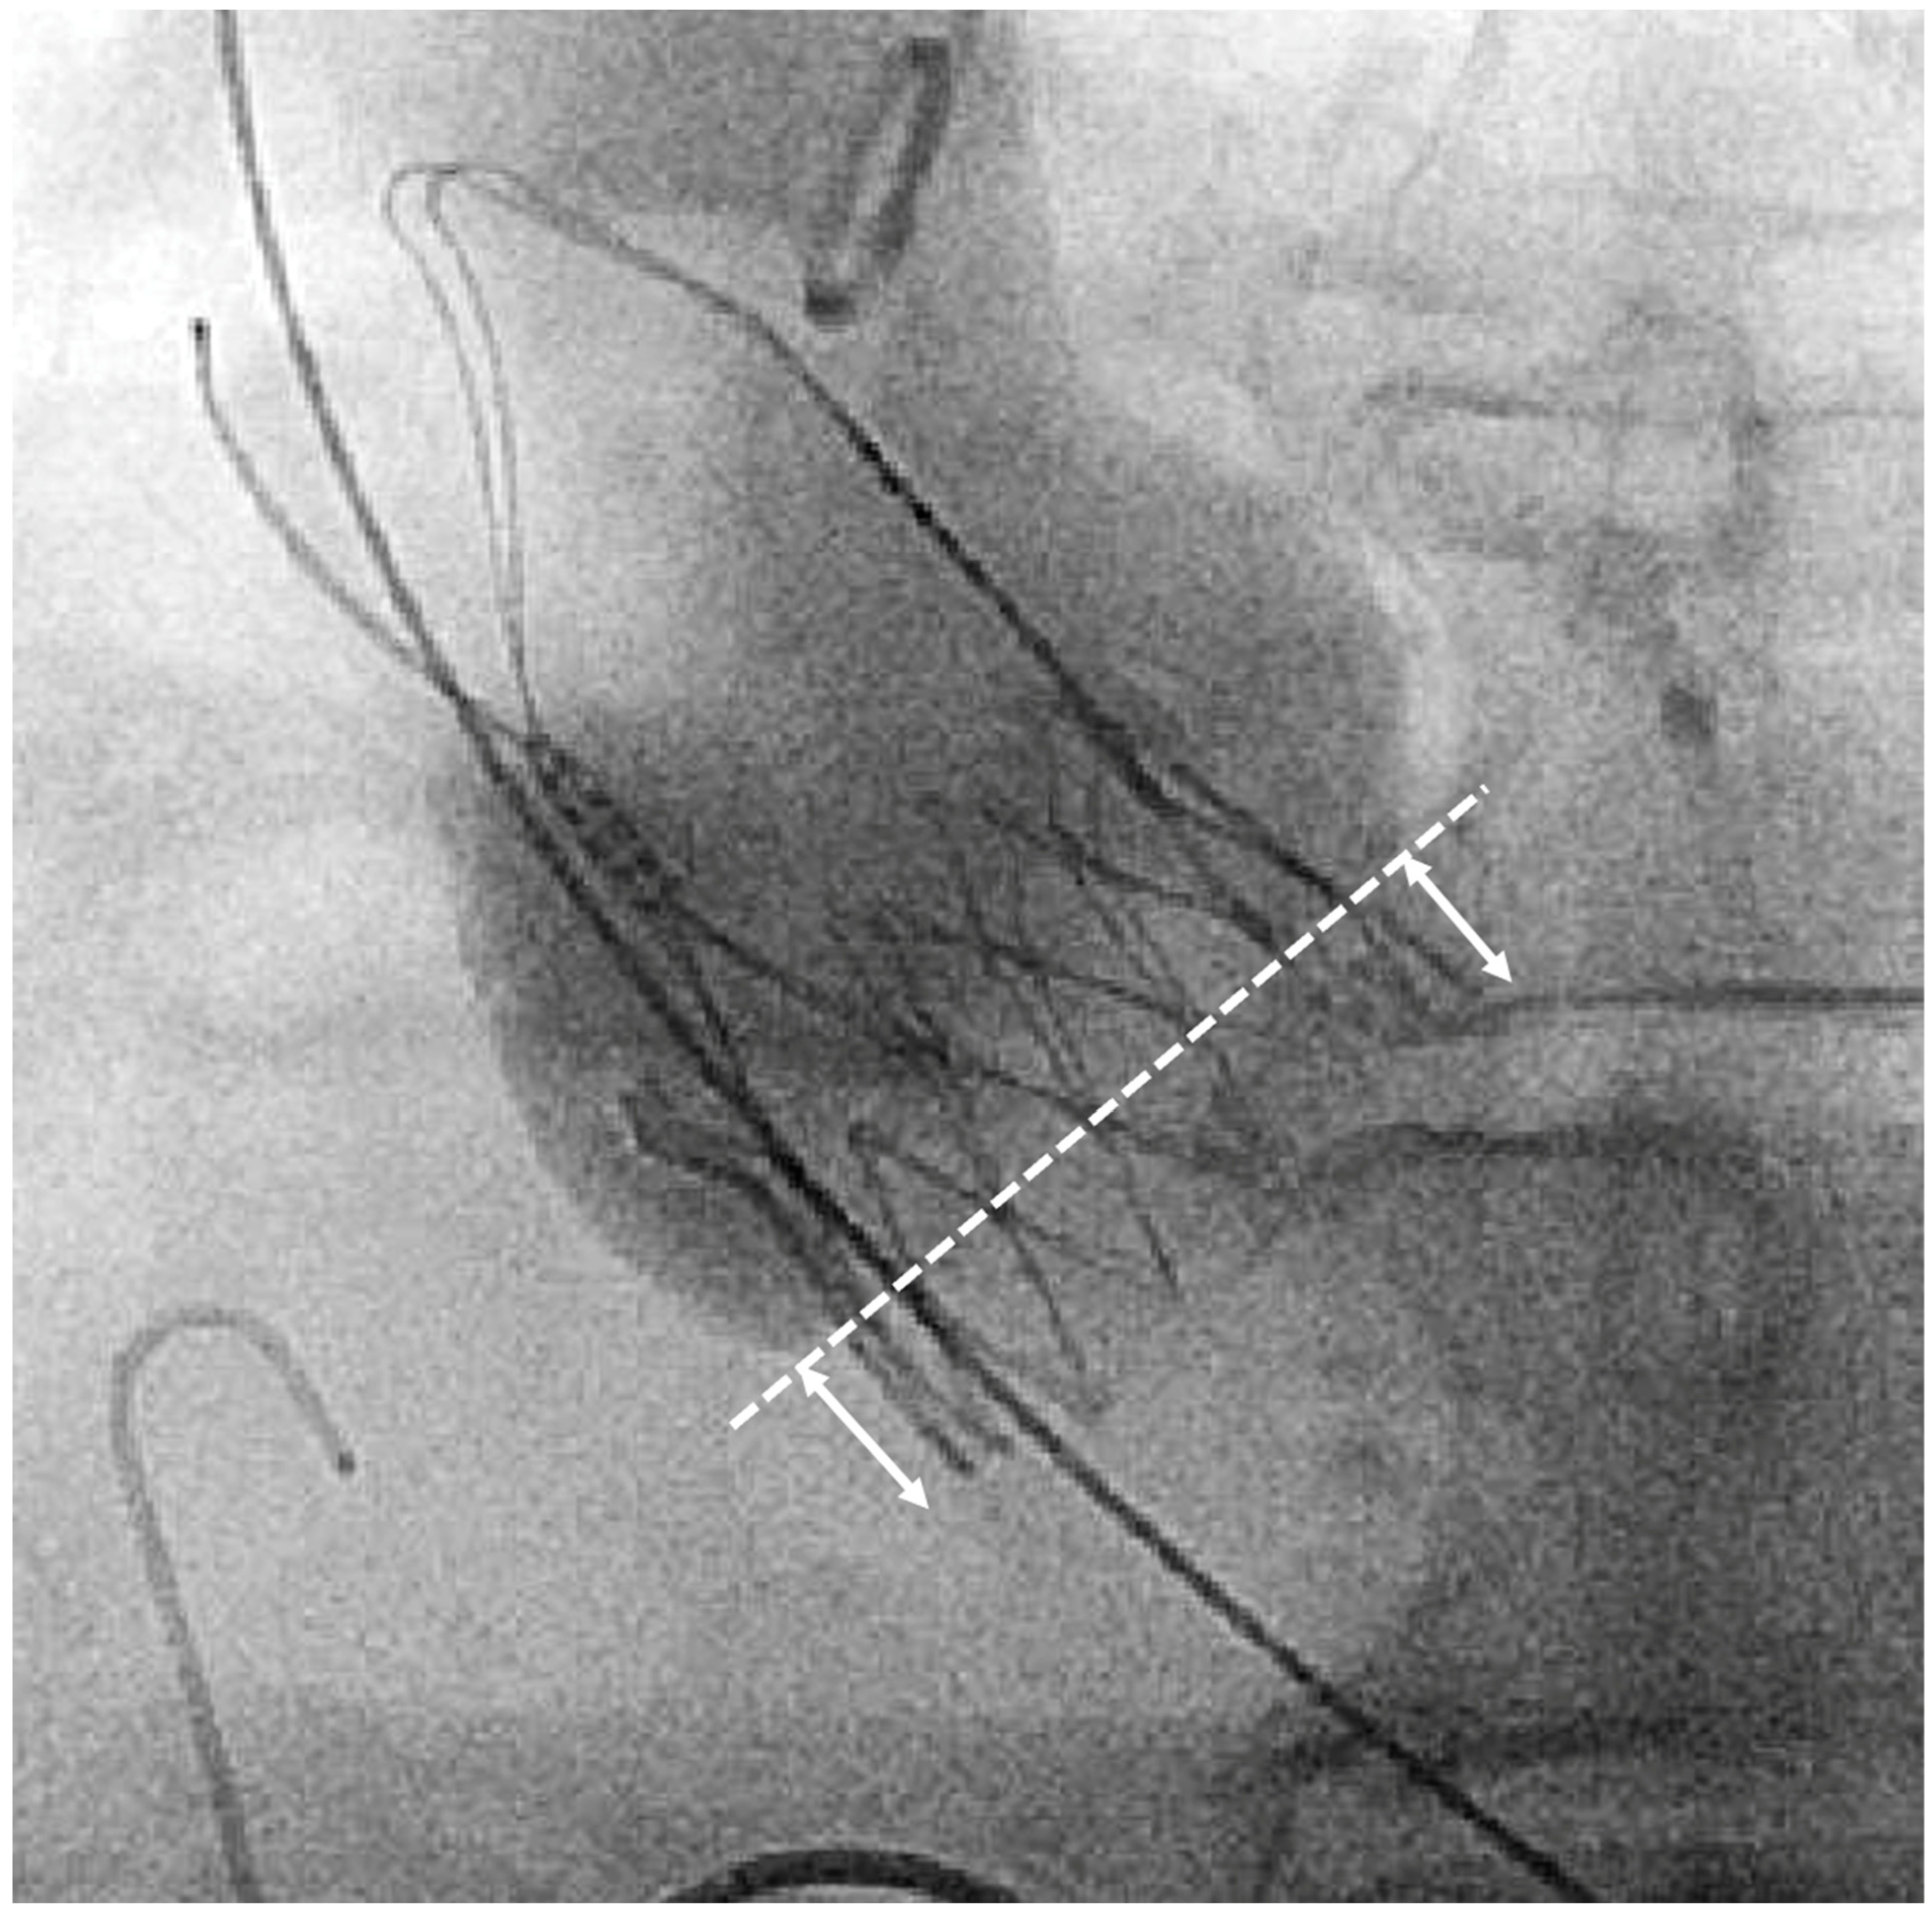

2.4. Definition and Measurement of Implantation Depth

Figure 1. Fluoroscopic measurement of implantation depth at non-coronary-cusp (NCC) in the cusp-overlap view. Arrows indicate implantation depth (ID).